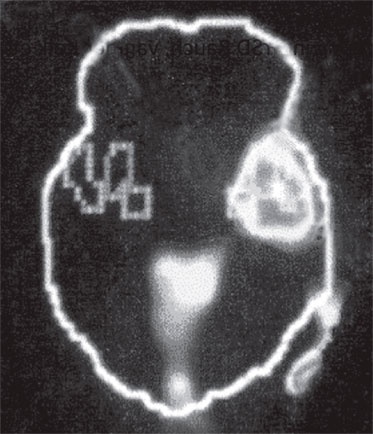

Б. Зрительная кора

Иллюстрация к книге — Тело помнит все [i_003.jpg]

Изображение мозга в процессе переживания травмы. Светлые пятна в лимбической коре (А) и зрительной коре (Б) соответствуют повышенной активности мозга в этих участках. На снимке (В) видна значительно пониженная активность речевого центра мозга.

Когда через эту процедуру прошли все восемь участников, Скотт Рауч вместе со своими математиками и статистиками взялся за создание составного снимка, по которому можно было бы наглядно сравнить активность мозга в нейтральном состоянии и в момент появления неприятных воспоминаний. Несколько недель спустя он отправил мне результаты, которые вы видите выше. Я приклеил эти снимки на дверцу своего холодильника в кухне и на протяжении следующих нескольких месяцев каждый вечер их разглядывал. Должно быть, именно так чувствовали себя первые астрономы, взглянув через телескоп на неизученное звездное скопление.